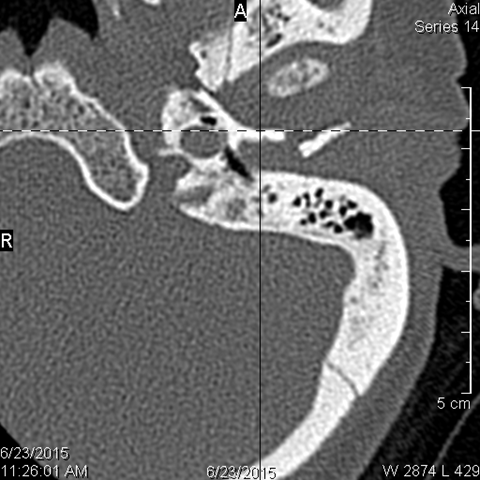

The condylar head and fossa as well as the temporomandibular joint space are fractured and/or dislocated. [Yes/No]

There is condylar fracture either within or outside of the joint capsule, or with or without involvement of the articular surface of the condylar head. [Yes/No]

There is evidence of radiodense intra-articular osteochondral fragments. [Yes/No]

There is bony injury or displacement of the external auditory canal and/or other evidence of temporal bone injury. [Yes/No]